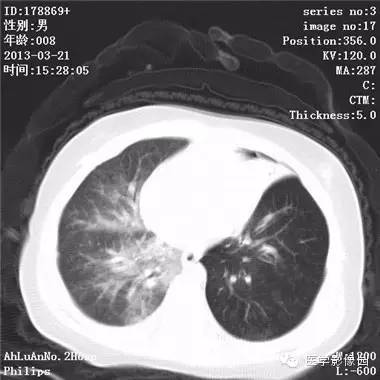

【病例】支气管异物1例CT影像表现

患儿男,8个月,呛咳,发热一周。实验室检查白细胞及中性粒细胞增高。

两肺肺纹理增多、增粗,右肺可见斑片状、片絮状模糊影,边界欠清;左肺上叶见楔形高密度影,内可见支气管征,尖端指向肺门;左肺下叶肺野透亮度增强;另见左肺主支气管内可见块状软组织密度影。

支气管异物(花生米)伴两肺炎症(追问病史,患儿奶奶层于一周前喂食患儿花生米,当时疑似“呛进去”,后来见好了也就没留意)。